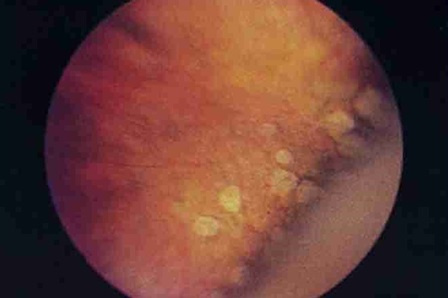

The type of dystrophy without participation of the vitreous is more benign. Such options include, for example, dystrophy of the type “cobblestone pavement”.

没有玻璃体参与的营养不良类型更为良性。 这样的选择包括例如“鹅卵石路面”类型的营养不良。

If in the dystrophy zone there are adhesions with the vitreous body, then often tractions (cords, adhesions) form between the modified vitreous body and the retina. It is highly likely that for any deformity it will pull the retina behind itself into the eye. Such adhesions, joining one end to the thinned area of the retina, many times increase the risk of ruptures and subsequent detachment. And this is all the chances of losing sight or degrading the optical quality of the eye to a few percent of the norm.

如果在营养不良区与玻璃体发生粘连,那么在修饰的玻璃体和视网膜之间通常会形成牵引力(绳索,粘连)。 对于任何畸形,极有可能将其自身后面的视网膜拉入眼睛。 这种粘连将一端连接到视网膜变薄的区域,多次增加了破裂和随后脱落的风险。 这是所有失去视力或将眼睛的光学质量降低到正常水平的百分之几的机会。

Such tears and dystrophies occur imperceptibly for the patient and are found not only in the near-sighted, but also in the far-sighted, and in people with absolutely normal optics of the eye.

这样的眼泪和营养不良对于患者而言是不明显的,并且不仅在近视眼中而且在远视眼中以及在具有完全正常的眼睛视力的人中都发现。

In myopic people, as a rule, the axial length of the eye is more than 24 mm (the average parameter, the measurement of which tells us about the progression of myopia). There is a risk that the eye, increasing (and an increase in the eye — this is, in fact, myopia) begins to pull the vitreous body (because the rest of the tissues stretch very little). Dystrophic chorioretinal processes on the periphery of the retina (“lattice degeneration”, “snail track”, etc.) lead to thinning of the retina and its ruptures.

通常,在近视人群中,眼睛的眼轴长度超过24毫米(平均参数,其测量值可以告诉我们近视的发展)。 存在眼睛增大(和眼睛增大,实际上是近视)的风险开始拉动玻璃体的原因(因为其余组织的拉伸很小)。 视网膜外围的营养不良性脉络膜视网膜病变(“晶格变性”,“蜗牛痕迹”等)导致视网膜变薄及其破裂。